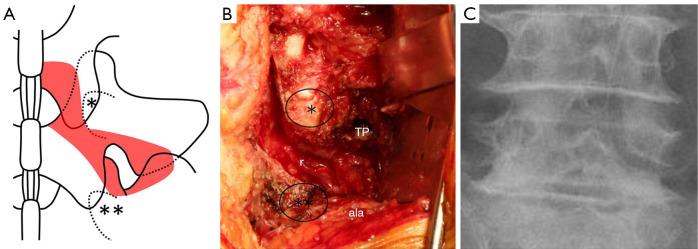

Radical decompression without fusion for L5 radiculopathy due to foraminal stenosis.

The highest incidence of lumbar foraminal stenosis (LFS) occurs in the L5-S1 segment and its anatomical features differ from those of other segments. Few previous reports have exhaustively assessed surgical outcomes after decompression surgery, limiting the materials to patients with LFS at the L5-S1 segment. We aimed to prospectively investigate instability and neurological improvement following our novel surgical technique for LFS at L5-S1, named "radical decompression" of the nerve root.

Patients with foraminal stenosis at L5-S1 who underwent surgery using our technique were prospectively evaluated two years postoperatively. The Japanese Orthopaedic Association (JOA) score and the JOA Back Pain Evaluation Questionnaire (JOABPEQ) were evaluated preoperatively and two years postoperatively. The following radiological parameters at L5-S1 were measured: lateral translation, sagittal translation, the difference in sagittal translation (DST) between flexion and extension, disc wedging angle, lordotic angle, the difference in lordotic angle (DLA) between flexion and extension, and disc height. Pre- and postoperative data were compared using paired -tests. In addition, the patients were classified into a disc group (Group D) and a non-disc group (Group ND) according to whether a discectomy was performed intraoperatively. Changes in each parameter before and after surgery were compared between the groups.